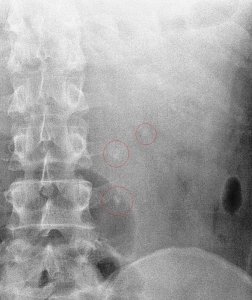

But the Urine FEME came back positive for RBCs, so my provisional diagnosis shifted towards urolithiasis. I downloaded the X-ray film and e-mailed it to a surgeon in Hospital Kuala Lumpur. He confirmed my suspicions by replying, “Congratulations, you got triplets!”.

The ultrasound report confirmed the diagnosis. I started treating myself by ingesting potassium citrate mixture 3 times a day to alkalinise my urine. I also had UFEME done regularly to monitor the presence of RBCs in the urine. A week later on 17th Feb, when the RBCs were no longer being detected in the urine, I had another KUB X-ray done.

The KUB on the 17th indicated that the bottom stone was still at the same site but the other two stones has come together and now were on top of each other. But there was no RBCs coming through, so either the bottom stone was blocking everything or the bottom stone had stabilised and was no longer cutting across the surface of my ureter, so no blood in the urine.